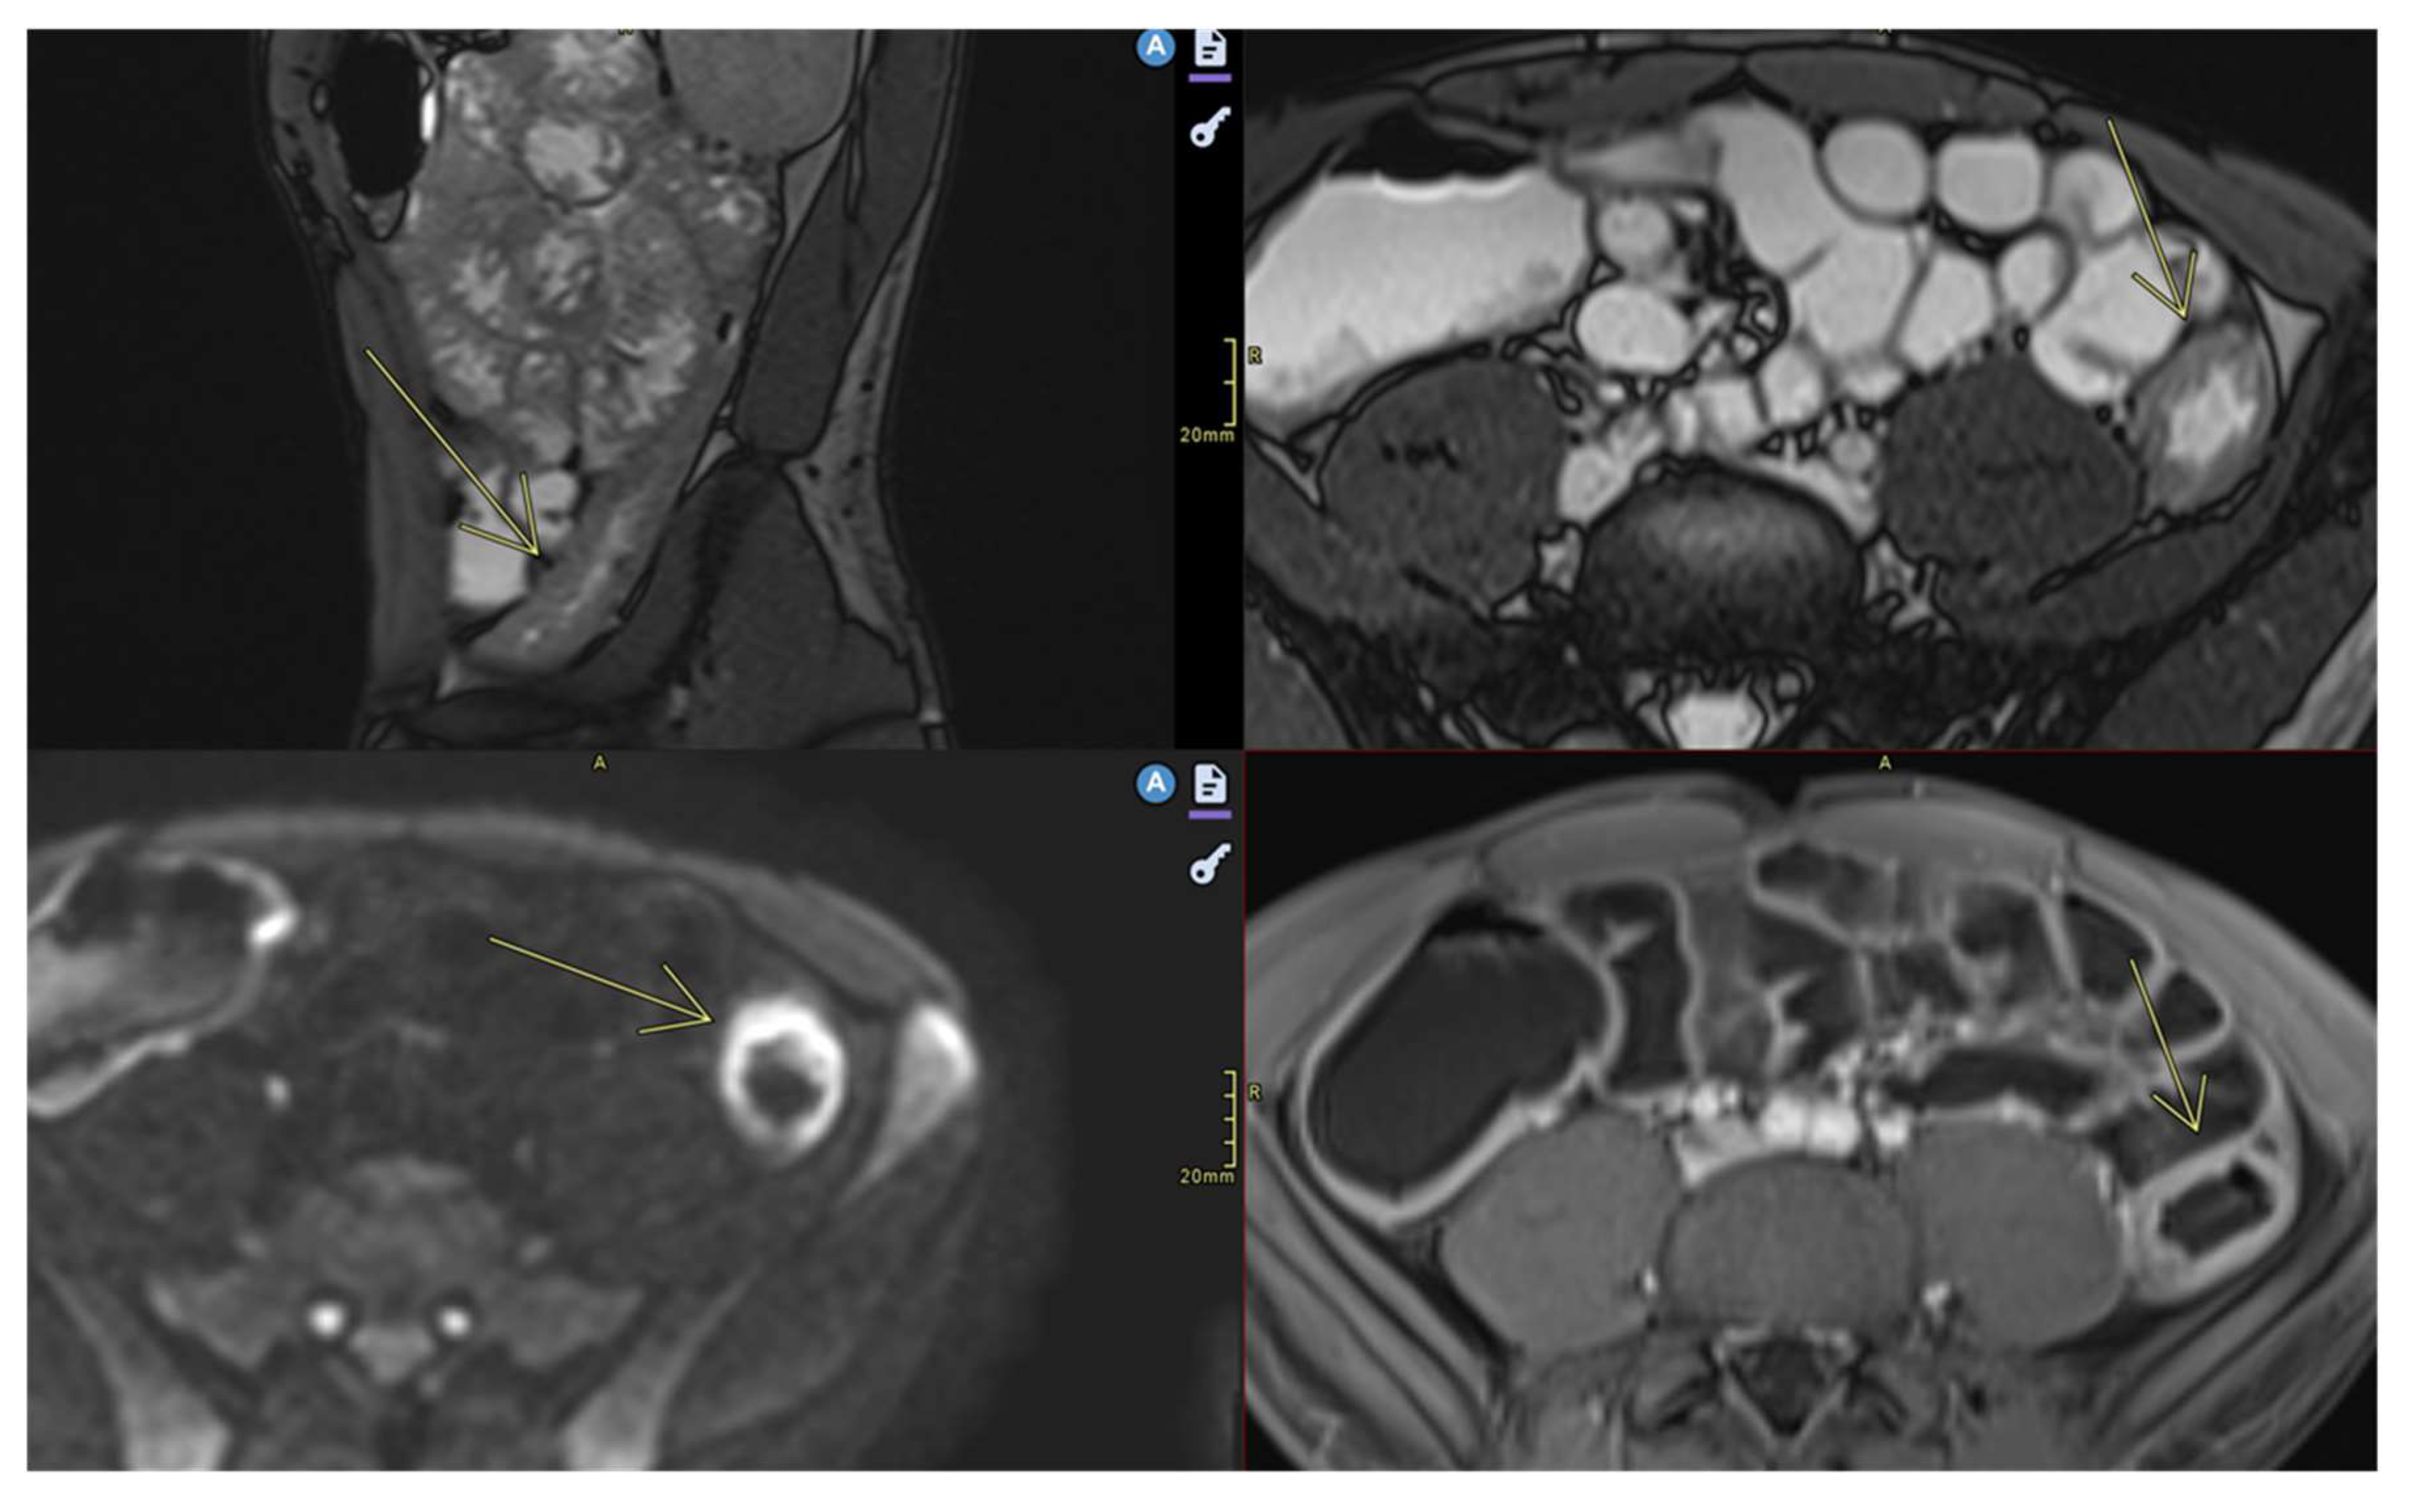

- Abcesses

- Abscesses are found in the abdominal cavity, intestinal wall, or perianal area[8]